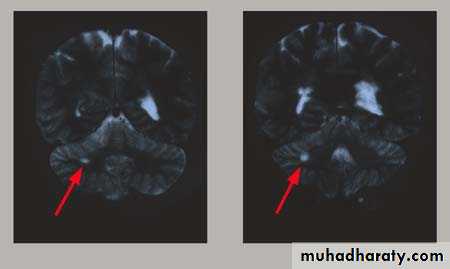

MRI FINDINGS

Patchy areas of white matter in paraventricular cerebral areasLesions in cerebellum/brainstem/ cervical and thoracic spinal cord

Gadolinium enhancement identifies active lesions

ABNORMAL MRI--CEREBELLUM